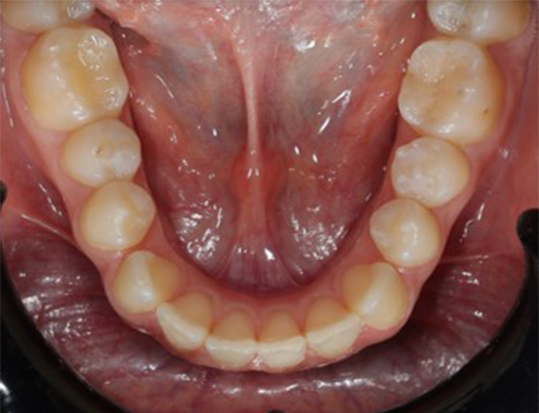

A 22-year-old female patient presented with a Class III malocclusion. She does not like her own profile. Her facial profile was straight with a slightly retrusive maxilla, the upper incisors were within normal inclination, and the lower incisors were retroclined. Bolton discrepency is on mandible for 6 teeth. A retruded upper lip and a normally positioned lower lip were noted. There was also a marked lack of midface support, and the constricted dental arches resulted in a narrow smile and pronounced dark buccal corridors.

Gaining overjet: Use forward-activating archwires to advance the proclined upper incisors and establish an adequate overjet.

Compensating proclination: Place retrocline brackets on UL2, UL1, UR1, and UR2 to counterbalance the created proclination.

Managing Bolton excess: Address the mandibular Bolton excess by increasing the mesiodistal expression on the upper canines, selecting procline brackets for UL3 and UR3.

Lower anterior control: To compensate for potential retroclination of the lower incisors during consolidation, use procline brackets on L3, L2, and L1 bilaterally.